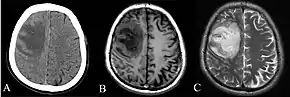

Depending on the course of infection, other severe manifestations develop. Approximately 1 to 5% of those infected develop inflammation of the brain and brain covering or brain abscess; 14 to 28% develop pyelonephritis, kidney abscess or prostatic abscesses; 0 to 30% develop neck or salivary gland abscesses; 10 to 33% develop liver, spleen, or paraintestinal abscesses; and 4 to 14% develop septic arthritis and osteomyelitis.[1] Rare manifestations include lymph node disease resembling tuberculosis,[10] mediastinal masses, pericardial effusion,[3] mycotic aneurysm,[1] and inflammation of the pancreas.[3] In Australia, up to 20% of infected males develop prostatic abscess which may manifests clinically as pain during urination, difficulty in passing urine, and urinary retention requiring catheterisation.[1] Rectal examination may find enlarged prostate.[3] In Thailand, 30% of the infected children develop parotid abscesses.[1] Encephalomyelitis not only happens in those with risk factors, but can also occur in healthy people without risk factors. Those with melioidosis encephomyelitis tend to have normal computed tomography (CT) scans but increased T2 signal by magnetic resonance imaging (MRI), extending to the brain stem and spinal cord. Clinical signs include: unilateral upper motor neuron limb weakness, cerebellar signs, and cranial nerve palsies (VI, VII nerve palsies and bulbar palsy). Some cases presented with flaccid paralysis alone.[3] In northern Australia, all melioidosis with encephalomyelitis cases had elevated white cells in the cerebrospinal fluid (CSF), mostly mononuclear cells with elevated CSF protein.[10]

Various imaging modalities can also help with the diagnosis of melioidosis. In acute melioidosis with the spreading of the bacteria through the bloodstream, the chest X-ray shows multifocal nodular lesions. It may also show merging nodules or cavitations. For those with acute melioidosis without the spread to the bloodstream, chest x-ray most commonly shows upper lobe consolidation or cavitations.[10] In chronic melioidosis, the slowly progressing of upper lobe consolidation of the lungs resembles tuberculosis.[10] For abscesses located in other parts of the body apart from the lungs, especially in the liver and spleen, CT scan has higher sensitivity when compared with an ultrasound scan. In liver and splenic abscesses, an ultrasound scan shows "target-like" lesions while CT scan shows "honeycomb sign" (abscess with loculations separated by thin septa) in liver abscesses.[10] For melioidosis involving the brain, MRI have higher sensitivity than a CT scan in diagnosing the lesion. MRI shows ring-enhancing lesions for brain melioidosis.[10]